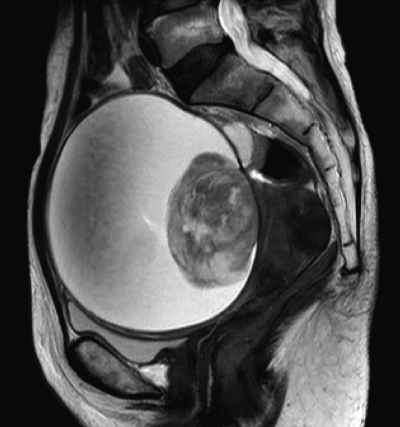

血液生化学所見:CEA 1.6 ng/mL(基準 5以下)、CA19-9 34 U/mL(基準 37 以下)、CA125 116 U/mL(基準 35 以下)。CRP 0.7 mg/dL。開腹手術を施行した。術前の骨盤部 MRI の T2 強調水平断像、矢状断像及び手術で摘出した組織の充実部分の H-E 染色標本を別に示す。

最終的な診断はどれか。

a. 明細胞腺癌

b. 傍卵巣囊腫

c. 漿液性囊胞腺癌

d. 成熟囊胞性奇形腫

e. チョコレート囊胞